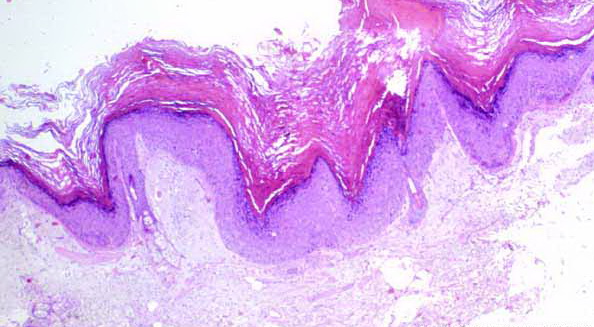

Papillomatosis in Verruca Vulgaris =التحلم في الثؤلول الشائع